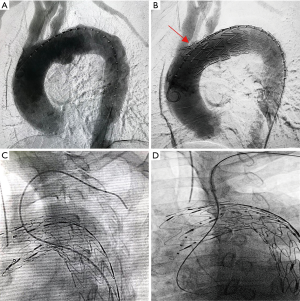

Adequate understanding of the anatomical structure via the pre-operative CTA was essential for the success of orientation. Digital subtraction angiography (DSA) was performed and the diameters of vascular branches were measured to design a fenestration with comparable size to the target vessels. The proximal part of the aortic stent-graft was unsheathed in vitro, measured, and marked by a sterile pen. Then, the fenestration was fashioned by a scalpel alongside the spiral support strut beside the eight-shaped marker (Figure 1A). The edges of the fenestration were kept neat, and all fragments were carefully removed (Figure 1B). Then, the fenestrated stent-graft was carefully reassembled. Guided by an extra-stiff guide wire, the stent-graft was inserted into the descending aorta via femoral access. After confirming that the “8”-shaped marker and the spiral strut of the stent-graft were aligned with the target vessel, the stent-graft was carefully released. Then, angiography was performed to check the results (Figure 3A,B).

The indications for stenting of aortic branches, already preserved by F-TEVAR, were as follows: (I) the IA and LCCA, being crucial brain supplying arteries, should always be stented by endografts, and (II) the following evaluation results showed that the LSA was not well preserved and required stenting: (i) intraoperative surveillance of bilateral blood pressure showed a significant blood pressure difference between bilateral brachial arteries; (ii) completion DSA showed poor blood flow through the orifice of the LSA. Either antegrade femoral access (Figure 3C) or retrograde brachial/carotid access (Figure 3D) could be used for delivery of endografts into the aortic branches. Femoral access required no extra brachial or carotid incisions, and was generally tried first.